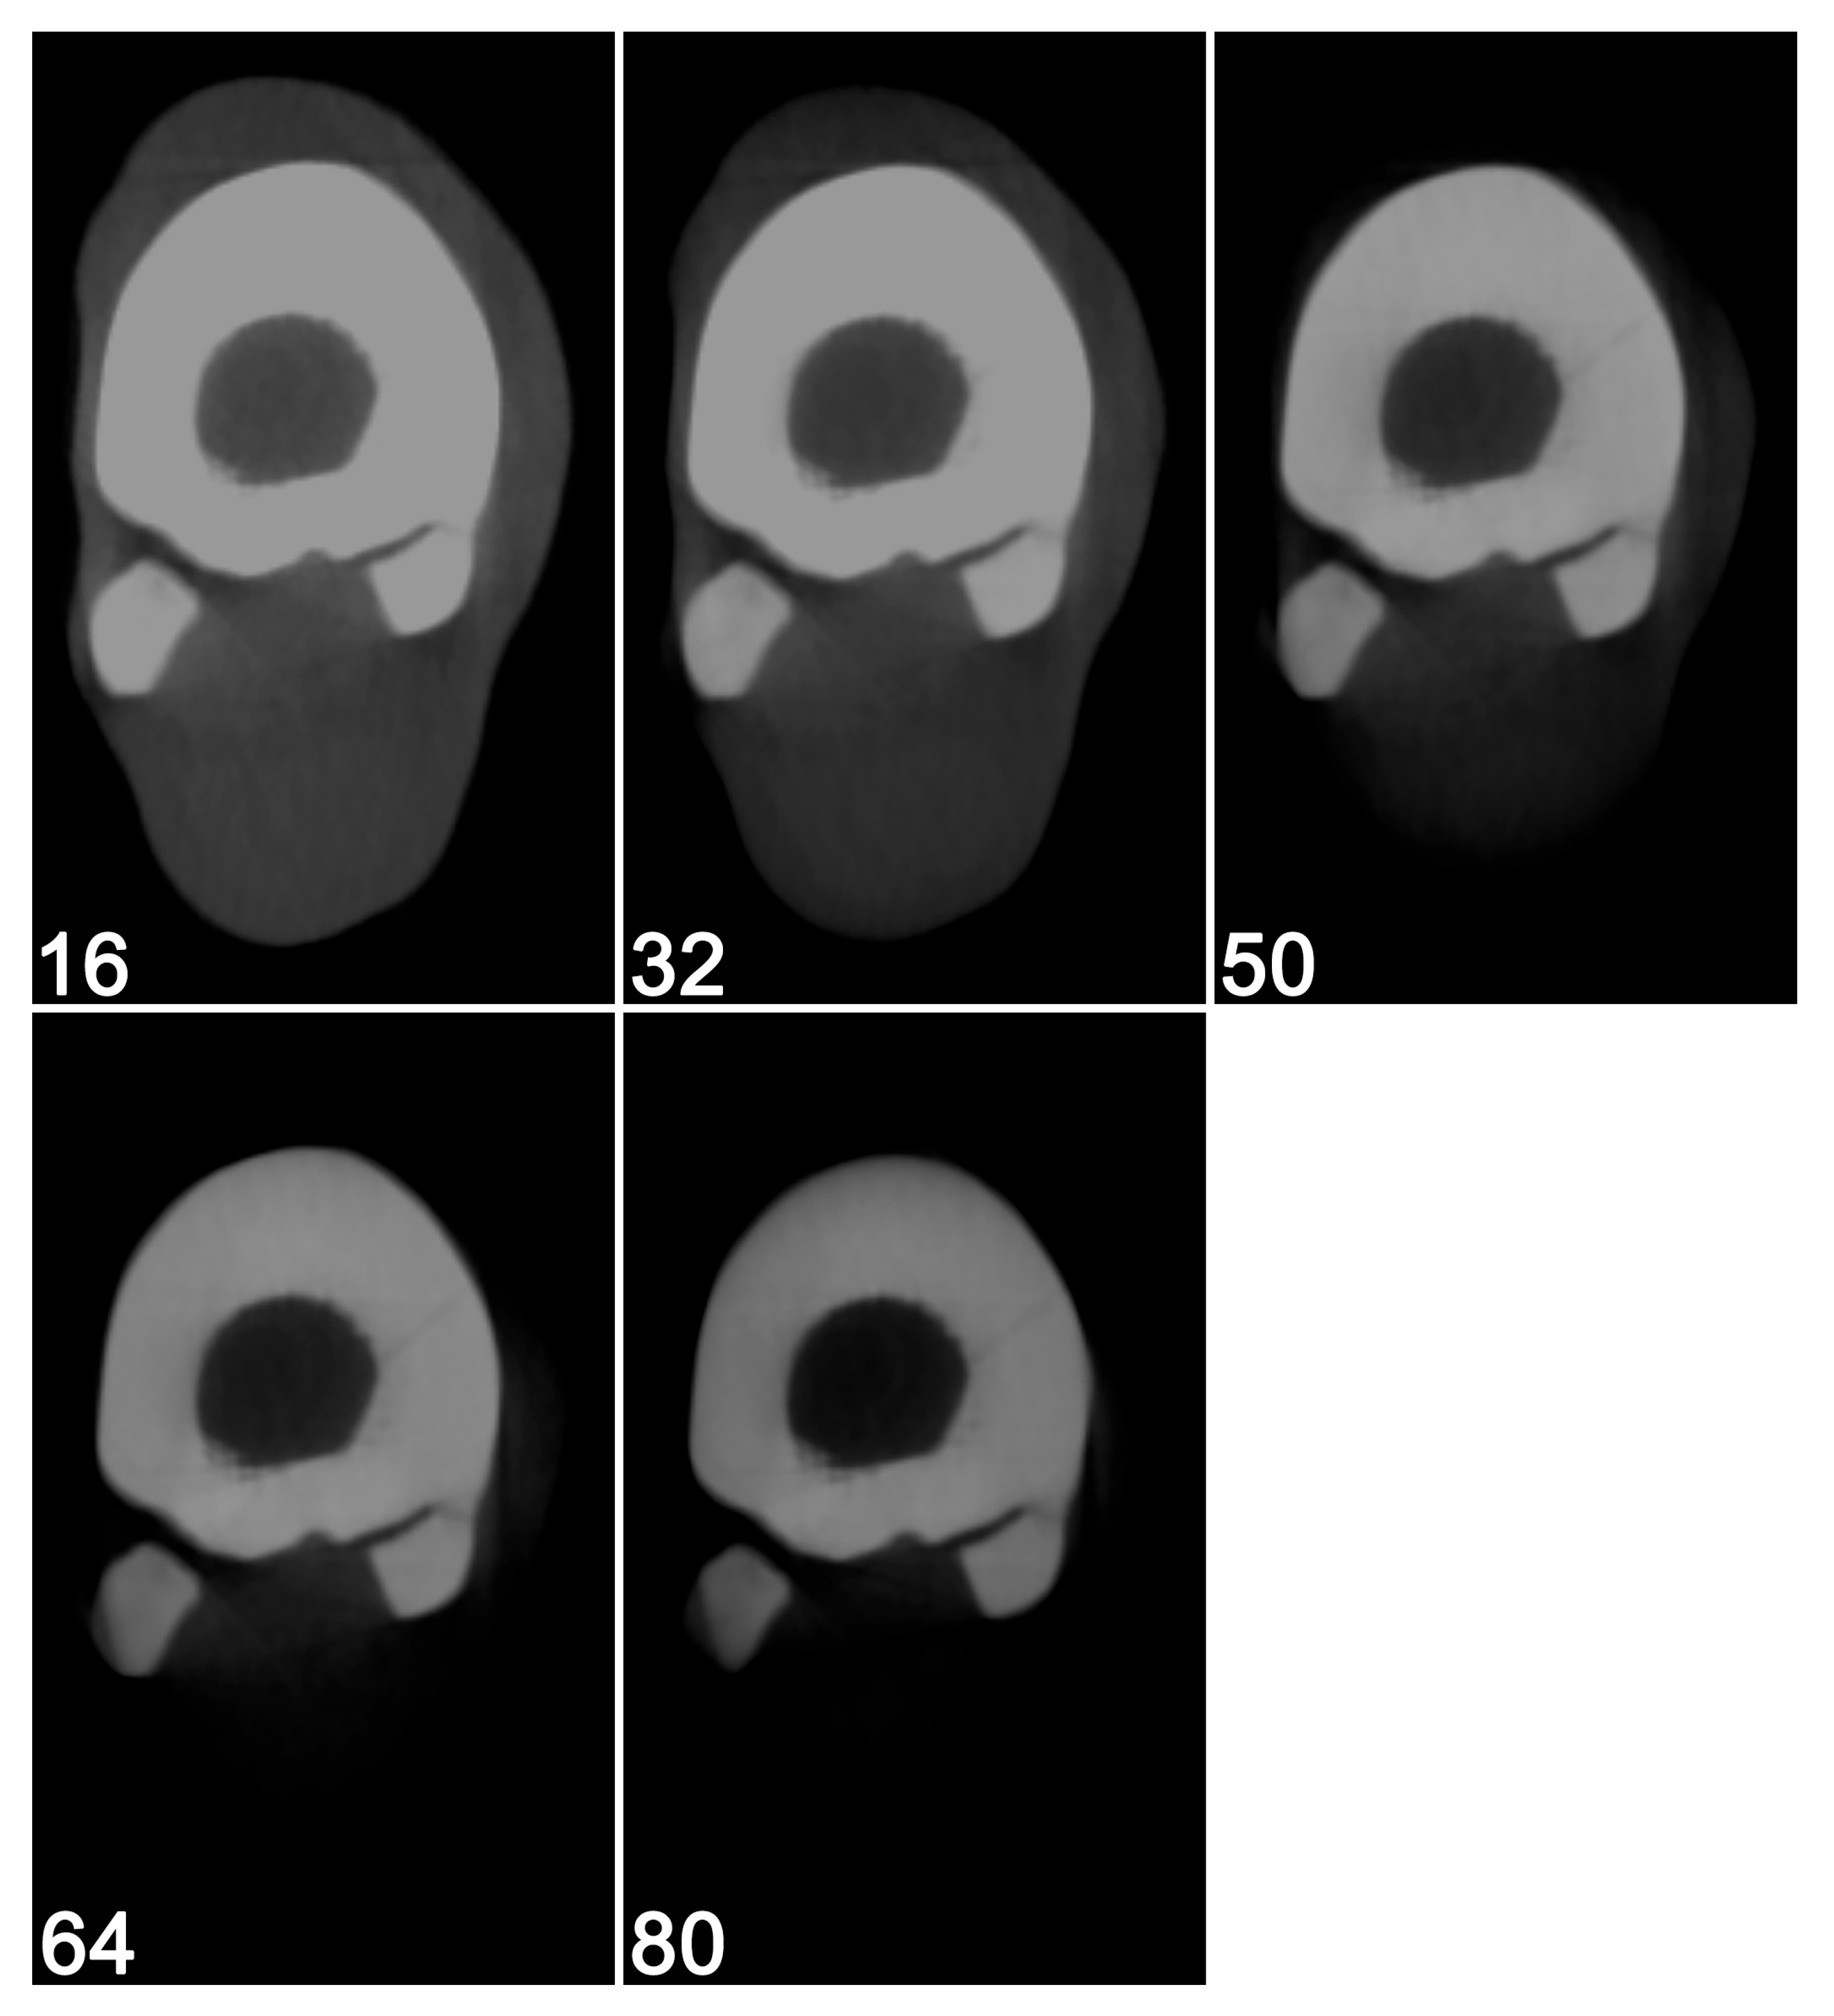

2.1. Image Acquisition and Reconstruction

3.1. Visual Image Quality Assessment

3.2. Clinical Case–Visual Image Quality Assessment